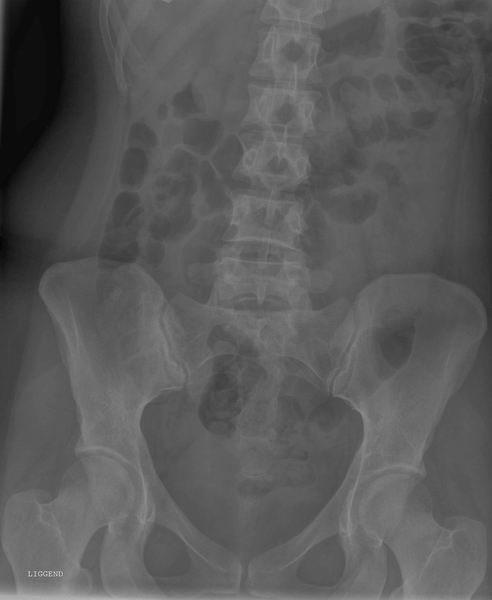

Bekken